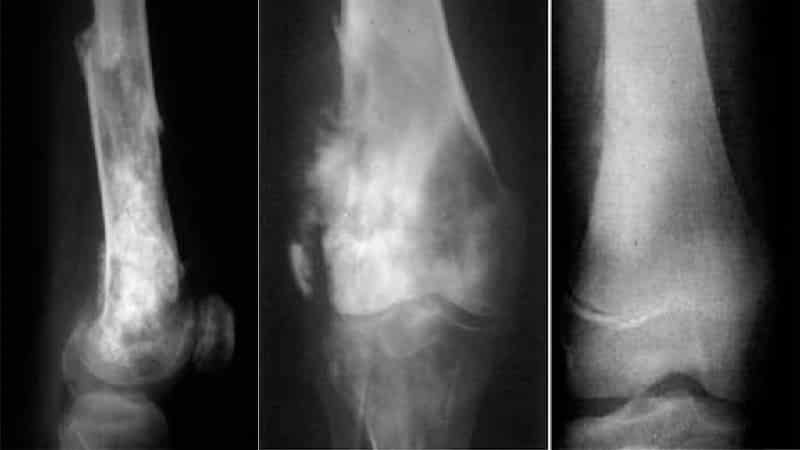

Основным методом диагностики злокачественных образований является комплексное рентгенологическое обследование. На основании результатов такого обследования можно обнаружить следующие признаки, указывающие на наличие опухоли:

- метафизарное расположение в длинных трубчатых костях;

- наличие склеротических и литических очагов в костной ткани, а также васкуляризация;

- очаги патологического остеогенеза в мягких тканях;

- нарушение целостности надкостницы с формированием «козырька» или «треугольника Кодмена»;

- игольчатый периостит — «спикулы» (разрастание периоста в виде иголочек, ориентированных перпендикулярно к поверхности кости);

- рентгенография легких позволяет выявить крупные метастазы.